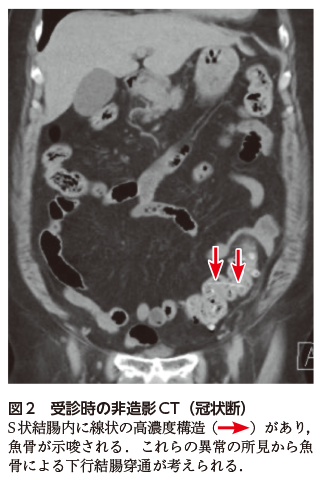

消化管穿孔/穿通と診断したら,その原因(腫瘍や異物)を考える.魚骨はCTで線状の高吸収域として描出されるが,軸位断のみではなく,thin slice(1 mm厚),冠状断や矢状断,multi planner reconstruction(MPR)像を確認することで,その構造を把握することができる(図2).

図2